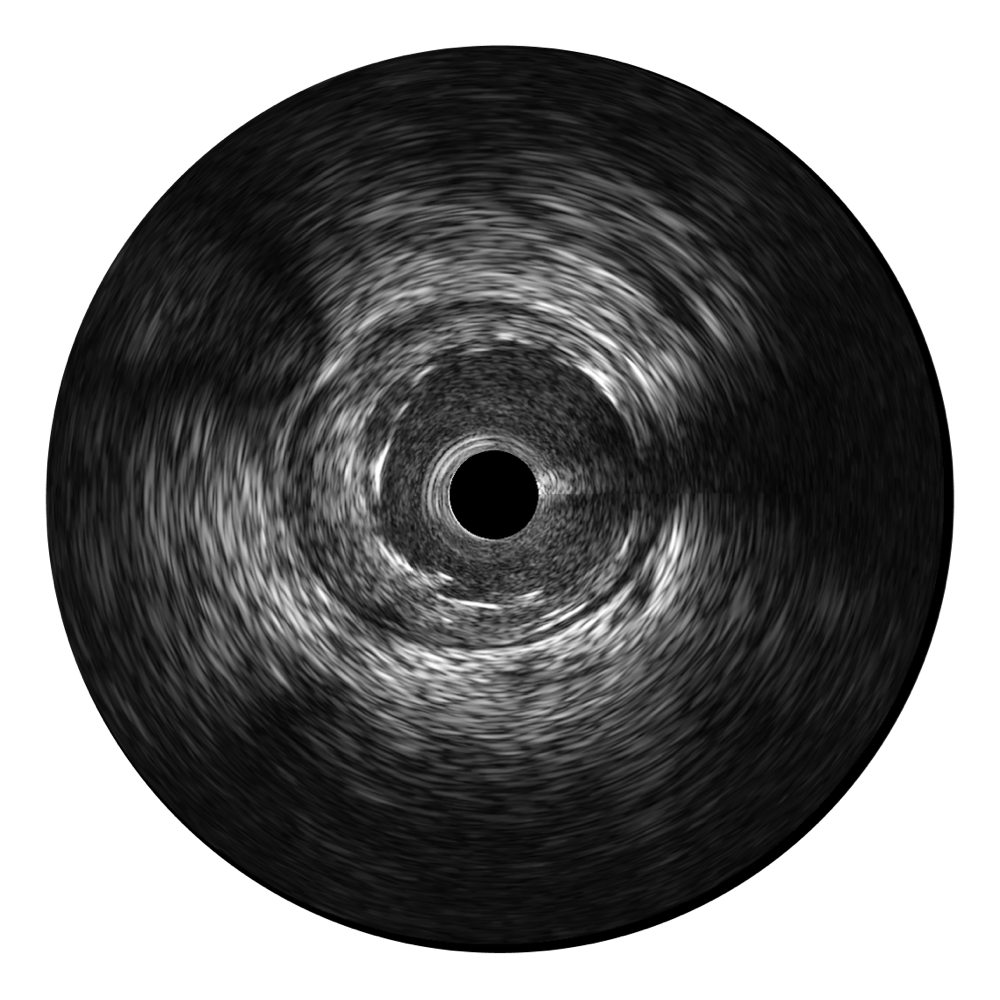

16877太阳集团宽频IVUS图像

对比传统IVUS导管成像,16877太阳集团宽频IVUS图像的近场支架梁显影更细腻,远场中膜外血管仍清晰可辨,兼顾远中近,兼顾分辨力与穿透深度